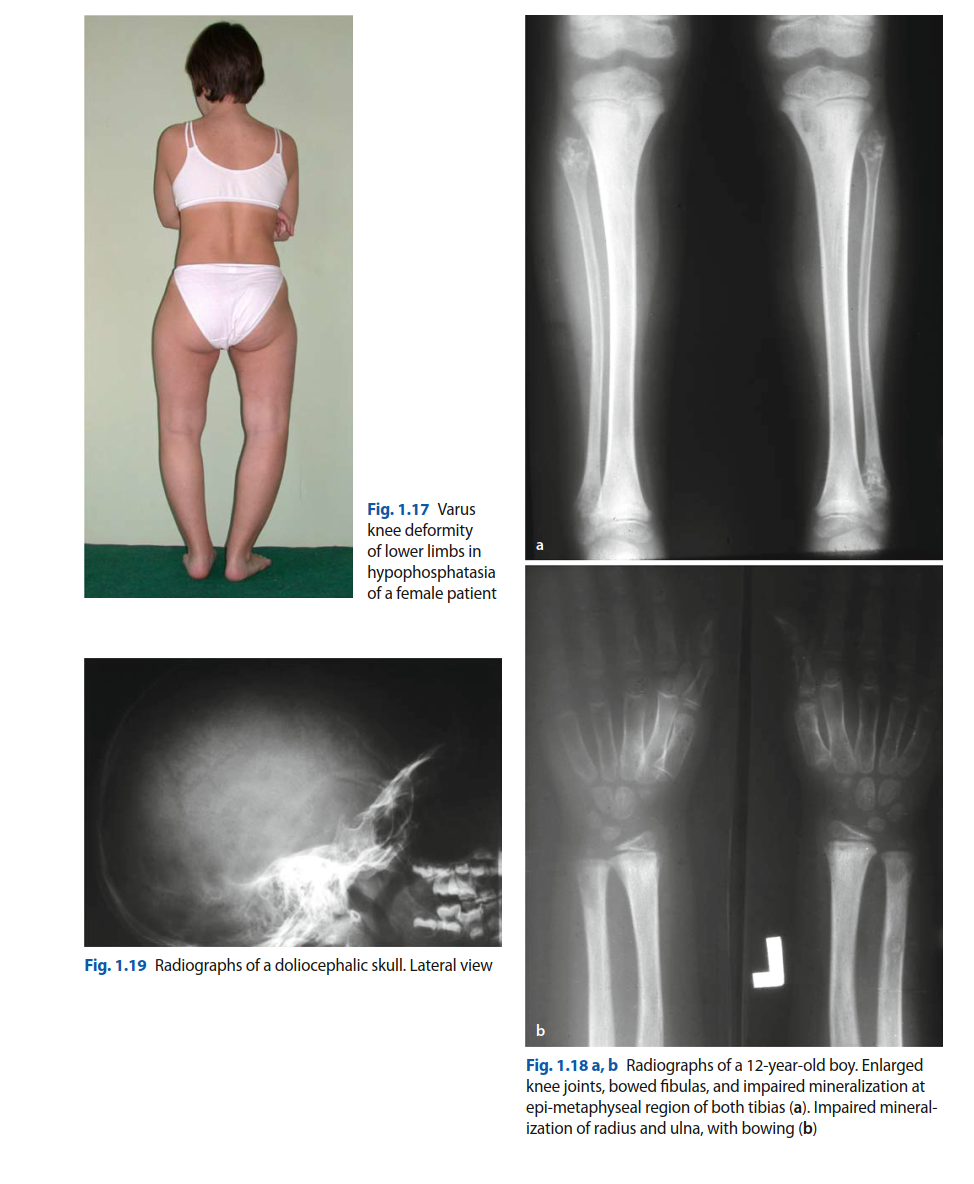

ORTHOPEDIC CASES / Hypophosphatasia (Congenital) The congenital form of hypophosphatasia is a rare error of m…